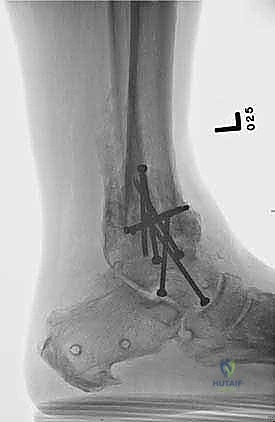

تثبيت مفصل الكاحل، أو "دمج الكاحل" (Ankle Fusion)، هو إجراء جراحي عالي التخصص يهدف إلى تحويل مفصل الكاحل المريض والمؤلم إلى كتلة عظمية واحدة صلبة وغير متحركة. الفلسفة الطبية وراء هذا الإجراء بسيطة وفعالة: "مفصل ثابت وبدون ألم أفضل بكثير من مفصل متحرك يسبب ألماً مبرحاً".

- تصحيح التشوهات بدقة: يسمح هذا المدخل بتعديل انحرافات الكاحل (سواء كان يميل للداخل Varus أو للخارج Valgus) وإعادته إلى المحور الميكانيكي الطبيعي للساق.

- تثبيت ميكانيكي حيوي أقوى: يتيح المدخل الأمامي وضع شريحة معدنية (Anterior Plate) على الجانب الأمامي للمفصل. من الناحية الميكانيكية الحيوية (Biomechanics)، يعتبر الجانب الأمامي هو "جانب الشد" (Tension side) أثناء المشي. وضع الشريحة هنا يوفر تثبيتاً فائق القوة ويقلل من معدلات عدم الالتئام.

- التخطيط الجراحي الرقمي: باستخدام صور الأشعة المقطعية، يقوم الدكتور هطيف بتخطيط الجراحة على الكمبيوتر لاختيار حجم المسامير والشرائح المناسبة بدقة مليمترية.

خطوات جراحة تثبيت مفصل الكاحل الأمامي بالتفصيل (Step-by-Step Surgical Procedure)

تُجرى العملية تحت التخدير العام أو النصفي (الشوكي)، وتستغرق عادةً بين ساعتين إلى ثلاث ساعات، وتتطلب دقة ومهارة فائقتين. إليكم الخطوات الجراحية كما ينفذها الأستاذ الدكتور محمد هطيف: